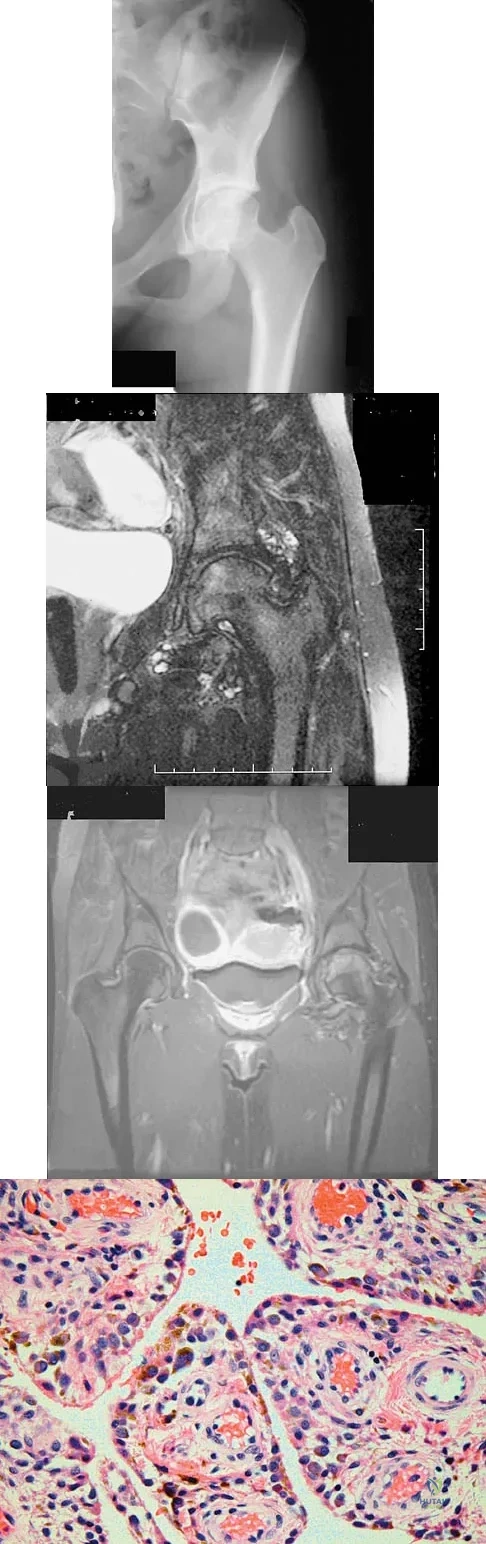

Figures 1a through 1c show the radiograph and MRI scans of a 16-year-old patient who has a painful hip. Examination reveals a significant limp, limited abduction and internal rotation, and severe pain with internal rotation and adduction. A biopsy specimen is shown in Figure 1d. What is the deposited pigment observed in this condition?

Explanation